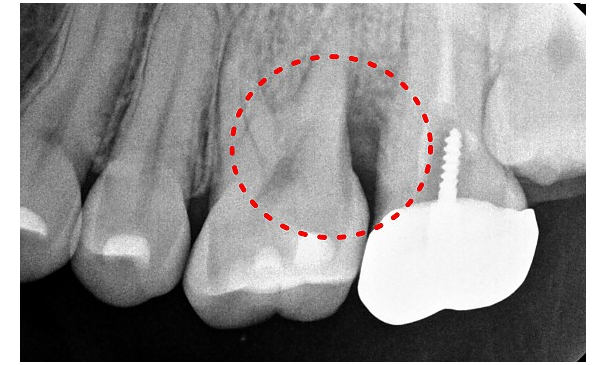

윤OO님 전후사진 | 치료 기간 : 6주

치료 전

치료 후